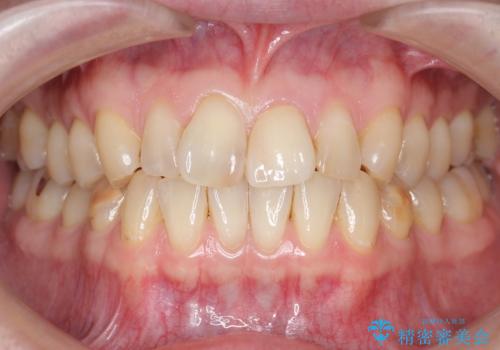

天然歯と見紛うほどの自然な仕上がりに喜んで頂けました。

クラウンの繊細なグラデーションや自然な表面性状・形態は熟練した技工士さんの技術の賜物です。

被せ物の種類:ジルコニアオールセラミッククラウン スペシャル